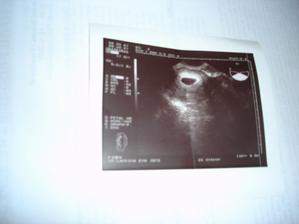

13.9. jsem dělala první testík a málem jsem přehlédla tu slabounkou čárku. Byl to menší šok, jelikož se o miminko už rok snažíme. Následující den jsem udělala další testík pro potvrzení a z nevolnosti už mi bylo více než jasné, že bude čárka silnější-a také že ano. První utz. 25.9. - 5+2tt mimi má 17mm. Druhý utz. 18.10. - 9+1tt mimi má 23,3mm. Třetí utz. 6.11. - 11+2tt. Čtvrtý utz. 29.11 - 14+4tt Malé má 16 cm. 16tt-16+3tt jsem přibrala 2 kila a začínám se pěkně cpát.Na utz. s námi byla nastávající babička. 20tt jsem zatím přibrala 4.5 kg. 21 tt další utz., váha 59kg. To s námi byl na utz. i tatínek. Začínající váha byla 53kg. 25tt kontrolní utz. 61kg. Miminko je zatím stále zadečkem dole.Tak máme 36tt, miminko už je otočené hlavičkou dole a já mám 65,5 kg. Přecházíme k doktorovi do nemocnice a čekáme kdy se prcek rozhodne přijít mezi nás, podle pana doktora to má být ještě před termínem 🙂